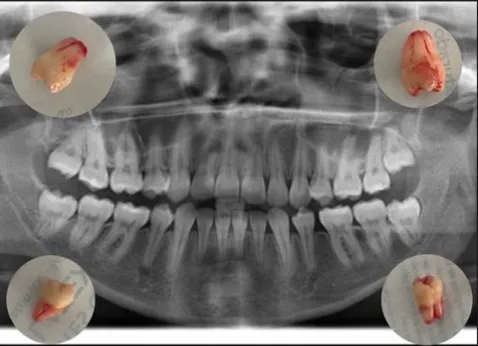

Vemos exactamente dónde están raíces, nervios y posición real.

Confirmamos si realmente necesitas la extracción y qué tan compleja será.

Radiografía panorámica.